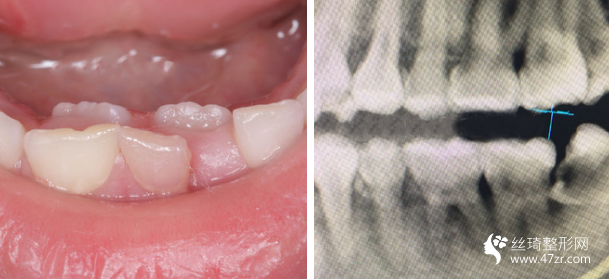

3.武漢伽美醫(yī)療美容醫(yī)院譚頔牙周病、烤瓷、牙美容行業(yè)專(zhuān)家案例展示

我的牙齒其實(shí)問(wèn)題不大,但是下面兩個(gè)牙齒被擠的歪了出來(lái),而且我 一直覺(jué)得我的嘴有點(diǎn)往外凸出,所以一直都有矯正的想法,朋友在他 們家做的貼面,推薦給我說(shuō)薇琳醫(yī)生很專(zhuān)業(yè)的,所以我也就過(guò)來(lái)了。 首先做了檢測(cè),然后設(shè)計(jì)了方案,取模,然后根據(jù)自己的牙齒情況制 定矯正器。 耐心等待我矯正器的到來(lái)。

很感謝我遇到了不錯(cuò)的醫(yī)生,在這方面臨床經(jīng)驗(yàn)比較豐富,醫(yī)生說(shuō)我的矯治過(guò)程進(jìn)展的較為順利,矯正速度真的是較為快呢,牙齒不齊整體也在調(diào)整牙齒咬合狀態(tài)了。